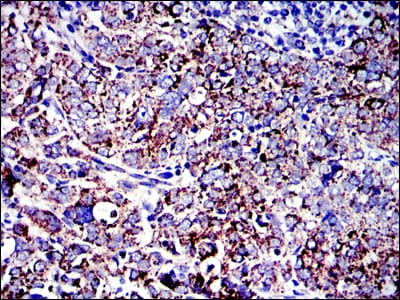

- Immunohistochemical analysis of paraffin-embedded human cervical cancer tissues using AIF mouse mAb with DAB staining.